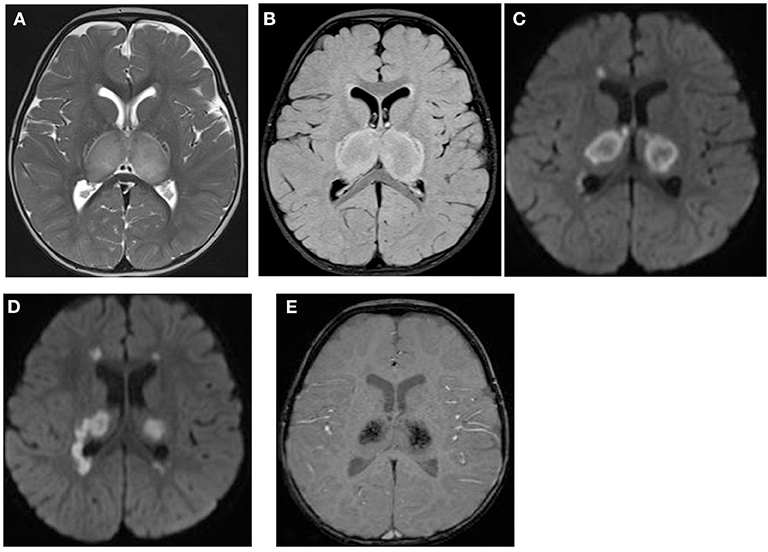

A total of 14 patients with ANEC were identified; two patients were excluded due to the inability to meet the ANEC radiological criteria. Patients' ages ranged from 10 months to 6 years (mean 30.92 months, median 22 months, standard deviation 20.63). Nine patients (75%) were female. All patients presented with preceding febrile illness in the form of upper respiratory tract infection (URTI) symptoms, or gastrointestinal symptoms in the form of vomiting or diarrhea, and altered level of consciousness. Seizures were the initial presentation in eight cases (66.7%). Brain imaging was carried out using Axial, Sagittal, and Coronal T1,T2, FLAIR, diffusion, and susceptibility weighted images which showed characteristic high signal intensity on axial T2 and FLAIR with variable degree of involvement of both thalami in all cases. Diffusion restriction was also seen, while the susceptibility sequence showed dark signal intensity with blooming, indicating hemorrhagic changes. Out of 12 patients, five (41.7%) had brainstem involvement. Follow up brain MRIs were done 2–3 months after the initial presentation, which showed signs of improvement on 33.3%, and 66.7% (n = 8) showed no signs of improvement. The clinical and radiological presentations are summarized in Tables 1, 2. Figures 1–4 show brain MRIs for selected patients.

Figure 1. Brain MRI. Axial T2 (A), FLAIR (B), diffusion (C,D), and susceptibility (E) weighted images. There are swelling and abnormal high signal intensity of both thalami (A,B) with diffusion restriction (C,D) and dark signal intensity with blooming (E).